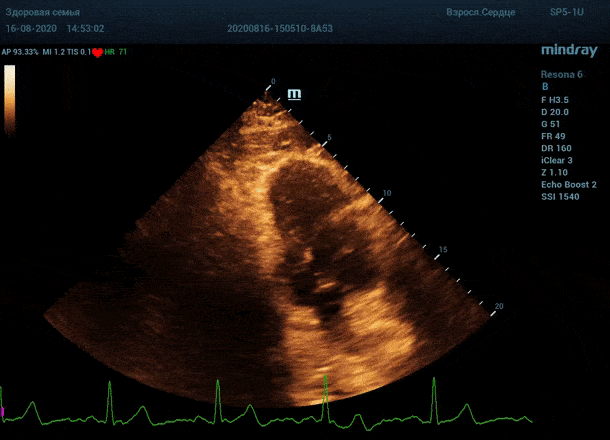

"Трудные пациенты" в эхокардиографии - явление не редкое. Часто встречается деформация грудной клетки или же площадь поверхности тела очень большая. Проблема акустического окна решается сменой положения тела пациента, снижением частот, изменением динамического диапазона и применением уникальных технологий производителя оборудования. Когда возможности ультразвуковой машины по оптимизации изображения исчерпаны, на помощь приходит оптимизация органа зрения.

Глаз каждого человека по своей природе уникален. Одни люди лучше видят белый и серый цвет, прекрасно различают все его оттенки. Другим людям проще ориентироваться в голубом, синем и фиолетовом диапазоне, холодных тонах изображения. Однако большинство прекрасно видит оранжевый цвет, и очень четко отличает его от черного – анэхогенного пространства.

Адаптивный колорайзинг - настоящая находка для опытного врача ультразвуковой и функциональной диагностики. Для тренированного глаза открывается новый мир четких контуров, совершенно другой взгляд на привычные структуры сердца.

Данная функция присутствует в большинстве моделей Mindray, с возможностью эхокардиографического исследования. Ограниченное ЭХО окно можно победить разными путями.